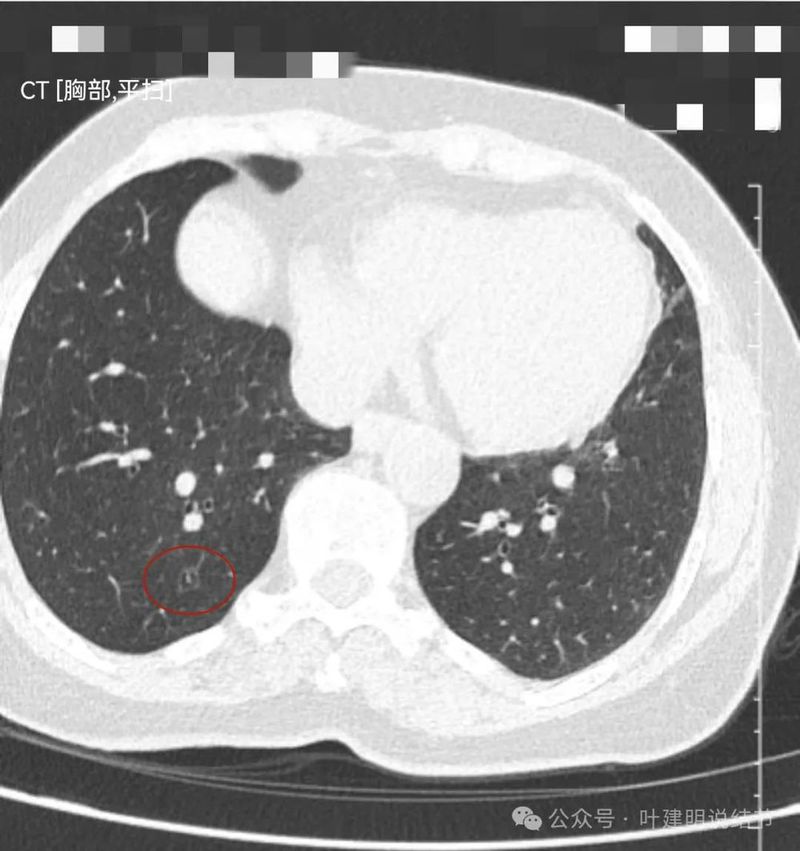

右下叶囊腔型病灶,囊壁较薄,内部有分隔,囊腔型肺癌不能完全除外,但肯定要先随访起。

右下另处囊腔灶,灶内有血管穿过,整体小且囊壁薄,再观察下。